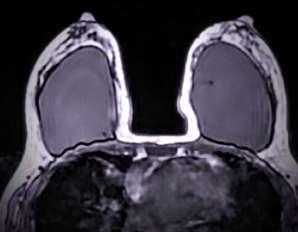

Elenfoquedelestudiodelasenferme‐dadesdemamasehatransformado enlosúltimosañosyaqueelnúmero decasosenincrementonoshadadouna perspectivadeevaluaciónintegraldela mama;porloqueesimportanterealizaruna personalizacióndelaatenciónparaintegrar undiagnósticooportunoenladeteccióndele‐sionessospechosas.

Laevaluacióndelamamainiciaenetapas tempranasconautoexploraciónalos18años, exploraciónclínicaapartirdelos25añosy utilizacióndeestudiosdeimagenquenoemi‐tenradiación,comoelultrasonidoenaquellas pacientesmenoresde40años.Posteriormen‐te,estádemostradoquelamastografíacons‐tituyeunmétodomuyconfiableydealtapreci‐siónparaladeteccióntempranadelcáncerde mama,antesdequeéstepuedaserdetectado mediantelaexploraciónclínica.

Losestudiosdeimagencomolamastografía, ultrasonidoyresonancia,permitenladetec‐ciónoportuna,lacaracterizacióndelesiones, evaluarlaextensióndelaenfermedadydar seguimientoalaslesionesmamarias.Conel propósitocumplirconlosobjetivosdeunpro‐gramadetamizajeparacáncerdemamapara nuestroequipoenCDIeneláreadeimagende lamama,esimportantetenerpresentequela calidaddelaimagenylaintegracióndevarios

métodosdeestudioesunapiezafundamental delproceso,porloqueresultanecesariollevar acaboprogramasdecontroldecalidad específico.

EnCDIcontamosconunmastógrafodigital, ultrasonidodealtaresolución,resonancia magnéticaconantenaespecíficaparamama, ademásdelarealizacióndeprocedimientos invasivoscómotomadebiopsiasymarcajes.

Laevaluacióndelaspacientesiniciarealizan‐dounanálisisdelosantecedentesderiesgo parapoderdeterminarunporcentajederiesgo alpadecimientodecáncerdemama,realizan‐doestudiosdeimagenacordealaevaluación clínica,edadycontextodenuestraspacientes. Nuestroobjetivofinalesconseguirimágenes dealtacalidad,conladosisderadiaciónmás bajaposible,reducircostos,minimizando pérdidadetiempoydetectandodeforma tempranalesiones,paraquelapacientepue‐danbeneficiarsedelaaplicacióndeprocedi‐mientosytécnicasqueofrezcanunamayor expectativa,tratamientosoportunosymejor calidaddevida.

Comopartedelmanejointegralutilizamos métodosdemarcajeespecíficoparalesiones nopalpablesdelamama,utilizandounaguía delocalizaciónoarpónensitiosespecíficos delamama.Lasbiopsiasymarcajessonpro‐

cedimientosdemínimainvasiónqueno requierenanestesiageneralnihospitalización paraelestudiohistológicodeltejidoquenos daundiagnósticohistopatológicodelas muestrasanalizadas.

Laresonanciamagnéticaesunmétodoque noutilizaradiaciónionizanteyproporciona informaciónmorfológicayfuncionalatravés delainyecciónendovenosademediode contraste.Estemétodocuentaconindicacio‐nesespecíficasenlatipificacióndelcáncer, valoracióndemárgenesdespuésdeescisión detumorprimario,búsquedadeprimario oculto,asícomométododedetecciónen pacientedealtoriesgo,etc.